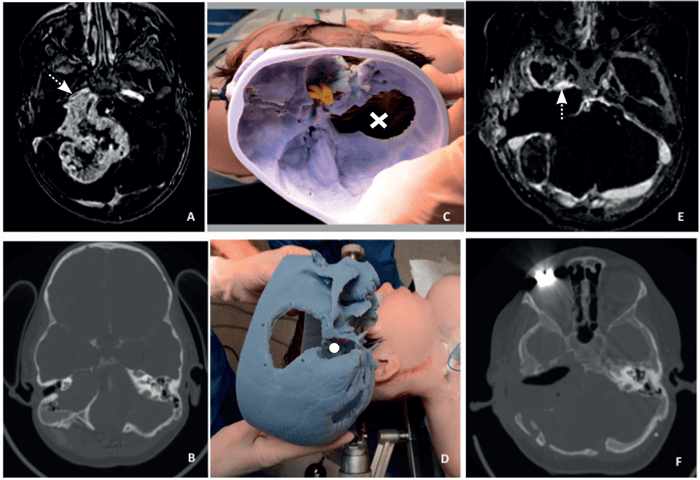

Figure 1. The preoperative MRI (A) and CT (B) of a patient with a right giant jugular schwannoma with immediate proximity to the right internal carotid artery (white arrow). We used the 3D-print intraoperatively (C and D); here shown in comparison with the patient’s positioning at the start of a staged procedure with part of the previous scar visible as well as the previous posterior craniotomy (X) and the cavity of the transpetrous approach (white dot) on the model. Finally, the MRI (E) and the CT (F) show the postoperative outcome with an extensive dissection and minimum residual on the internal carotid artery (dotted arrow).

The 3D-prints (see Figures 1-3) are based on a high-resolution computed tomography (HRCT) scan of the temporal bone and the skull with a thickness of 0.5-0.6 mm (scans performed in various scanners in our department). The patient’s HRCT scan is exported into a 3D software package (Mimics, Materialise, Leuven, Belgium) to convert in to a digital imaging and communications in medicine (DICOM) file to which can be manipulated to reduce and target certain areas. The import of the DICOM file can easily and quickly create accurate 3D models. The software package allows the operator to anatomically analyse and virtually simulate surgery on screen. The final process involved exporting the 3D analysis and the printing of the 3D model. The stereolithographic file was exported to the 3D printer and the printing of model was finalised. We used the printer OBJET 30 (OBJECT 30, Stratasys, MN, United States) and rigid opaque photopolymers (Vero blue) as the printing material for our models; a material that allows detailed printing in blue colour (see Figures 1-3). The time needed for each 3D-model varied between 16 and 22 hours with an approximate cost of £340-£380 for every detailed model for an in-house production. Most of the time is associated with the actual printing, which is usually done overnight.

We primarily use the models for perioperative planning (see Figures 1-3) but also during the consultations to better demonstrate to the patients and their relatives the extent of the disease, the structures involved (internal carotid artery, bulbar nerves, facial nerve, otic capsule, sigmoid sinus and the jugular bulb) and the planned approach. The intraoperative use of the models is typically combined with navigation, when necessary, particularly in revision cases. We also use the 3D prints for teaching and training purposes to explain to our trainees and medical students the complex anatomy of the skull base.

Although the concept of 3D prints has been utilised in a few specialties, in skull base surgery it is still relatively unexplored, representing an emerging concept for teaching, training, planning and executing [2]. Such a concept comes with a very reasonable cost, considering the cost savings that a better-planned surgery has to offer. We found such models very useful for preoperative planning, particularly in revision or two-stage procedures, where the anatomic landmarks have been disrupted by both the pathology and the previous surgical intervention. Additionally, when it comes to a revision case, the skull base print can give, combined with navigation, a very accurate 3D understanding of the precise location of vital anatomical structures (see Figures 1 and 2).